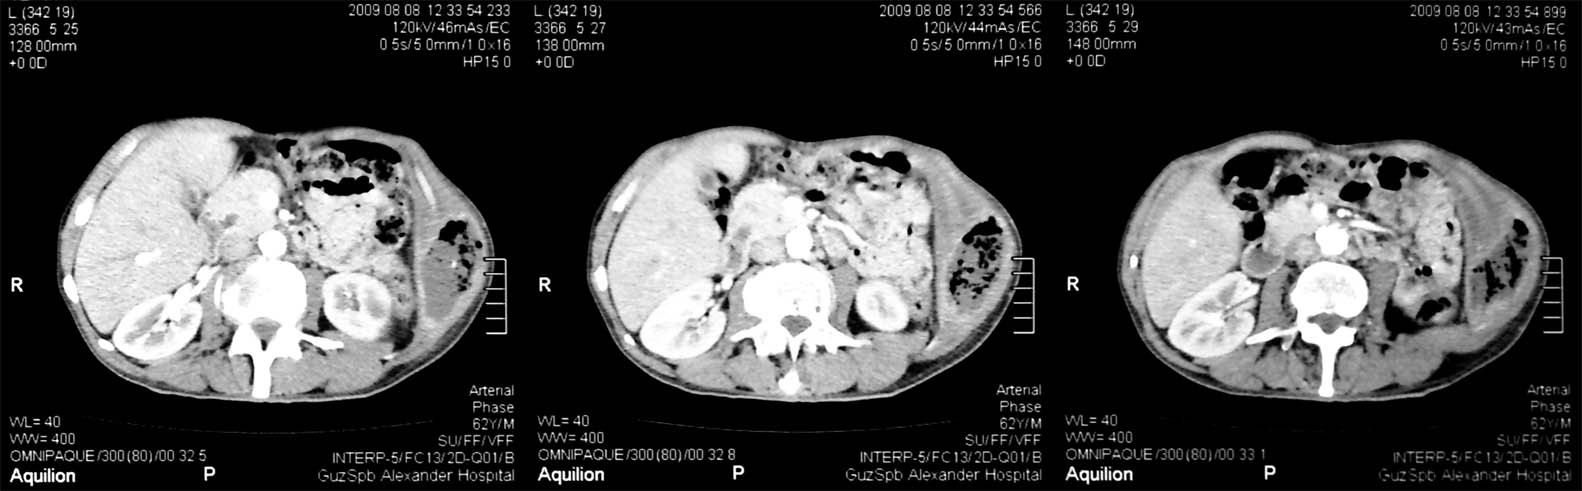

Здесь представлены КТ срезы брюшной полости и таза с контрастированием, выполненные через 2 года после травмы.

Венозная фаза

на серии кт определяются в средней трети левой почки ,латерально от ее ворот определяется гиповаскулярный участок с четкими ровными контурами .с поддавливанием чашечно-лоханочной системы,ограниченый капсулой почки ,неправильной вытянутой формы ,который в поздней венозной фазе не изменяет своей визуализации (д.д между кистой и кистозной формой почечно-клеточного рака).латерально от левой почки в мягких тканях определяется большой участок со сниженной денситометрической плотностью,размерами - 53х117мм ,с включениями газа и кольцом периферического усиления,с дренажом(вероятнее всего крупный абсцесс).печень увеличена в размере,селезенка с включениями кальция .размеры поджелудочной железы в пределах нормы,холедох и вирсунгов проток без патологии.надпочечники нормальных размеров,без изменений.в области левого тазобедреного сустава определяется участок деструкции с разрушением вертлужной впадины ,головки и шейки бедренной кости ,смещением повздошной кости вверх и латерально на 111.1мм,с фрагментом головки левой бедренной кости .в левой повздошной кости определяются гиперостоз с обширным участком остеосклероза и мелкими участками остеолитической деструкции (смешанный тип).аналогичные остеолитические изменения в крыле правой повздошной кости и в головке правой бедренной кости (сужу по 3d).по медиальному контуру средней трети тела поздошной кости определяется разрушение замыкательной пластинки с вовлечением губчатого вещества на большом протяжении,в крыше и самой вертлужной впадине с мягкотканным компонентом ,с участками пониженной денситометричской плотности (вероятнее всего участки некроза),с мелкими костными фрагментами (что косвенно может подтверждать рост изнутри снаружу),с поддавливанием на большом протяжении органов малого таза,латерально -левая стенка мочевого пузыря утолщена.вывод :такие изменения могут быть как первичного так и метастатического характера .первопричина протрузии возможно врожденного характера(дисплазия) ,затем перелом усугубил процесс(посттравматическая протрузия).меня настораживает тот момент,что изменения в повздошной кости напоминают хронический остемиелит изначально .а затем появились изменения ,сильно напоминающие озлакочествление+изолированно крупный абсцесс